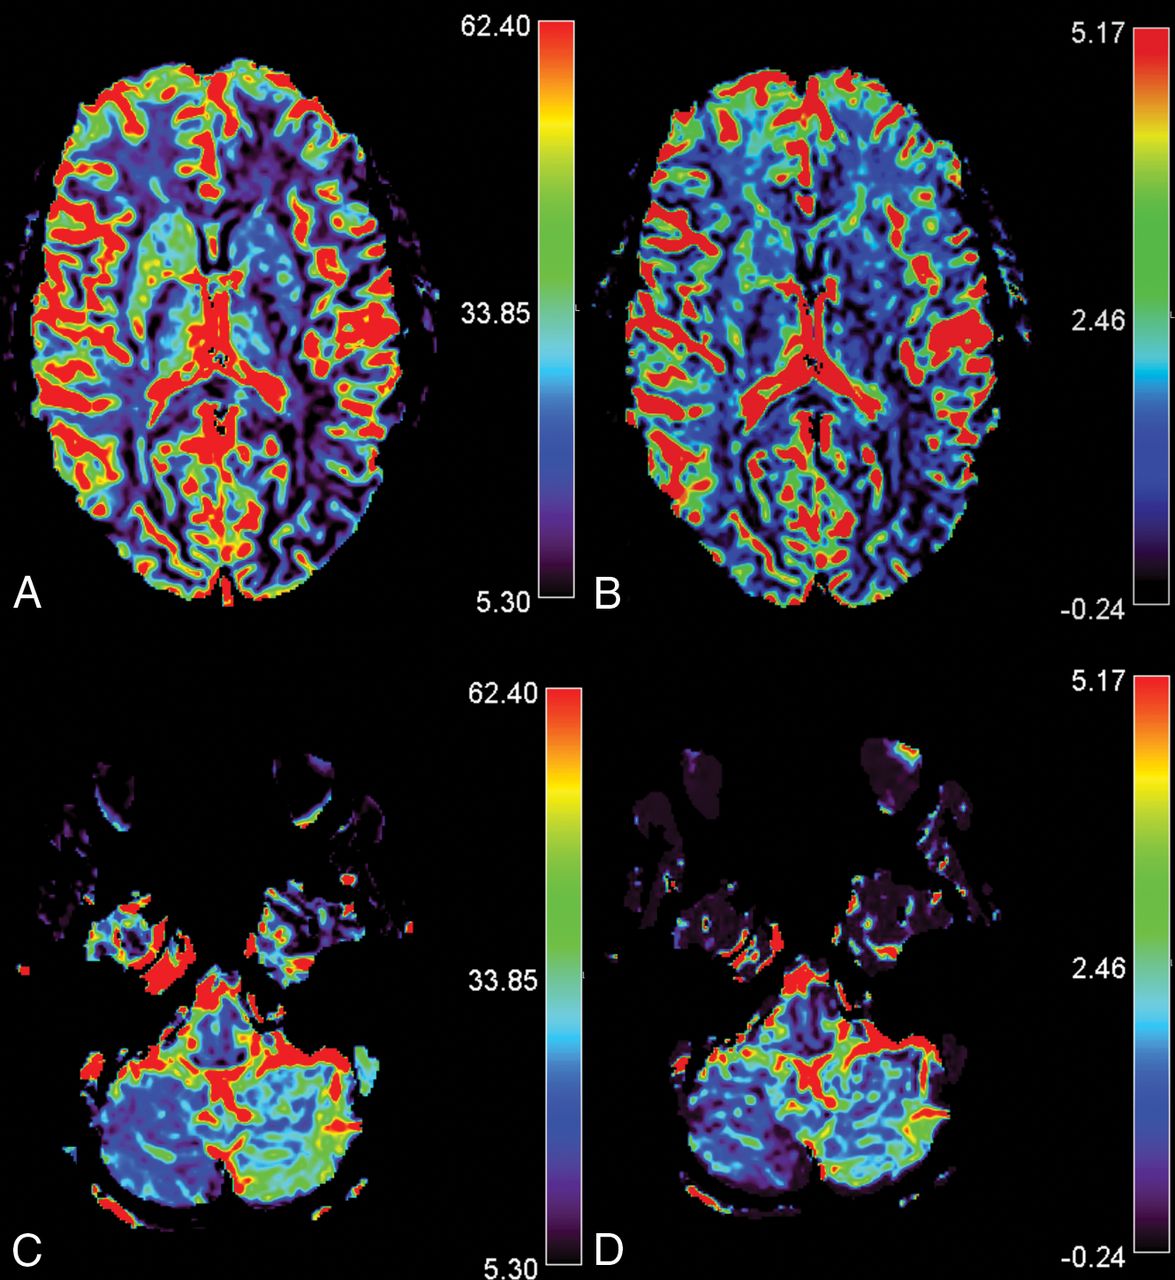

A sample description is provided in Fig 2.

CCD in a 14-year-old girl presenting with MwA and CCD. Slices A and C show rCBF images of the infra- and supratentorial brain, and slices B and D, rCBV images respectively. The patient presented with HCH in the right cerebellum with overt hemispheric perfusion asymmetry. Fourteen of 17 supratentorial ROIs in the left supratentorial hemisphere exceeded the AI threshold with lateralization of hypoperfusion contralateral to the cerebellum. Bars indicate relative values for CBV and CBF.